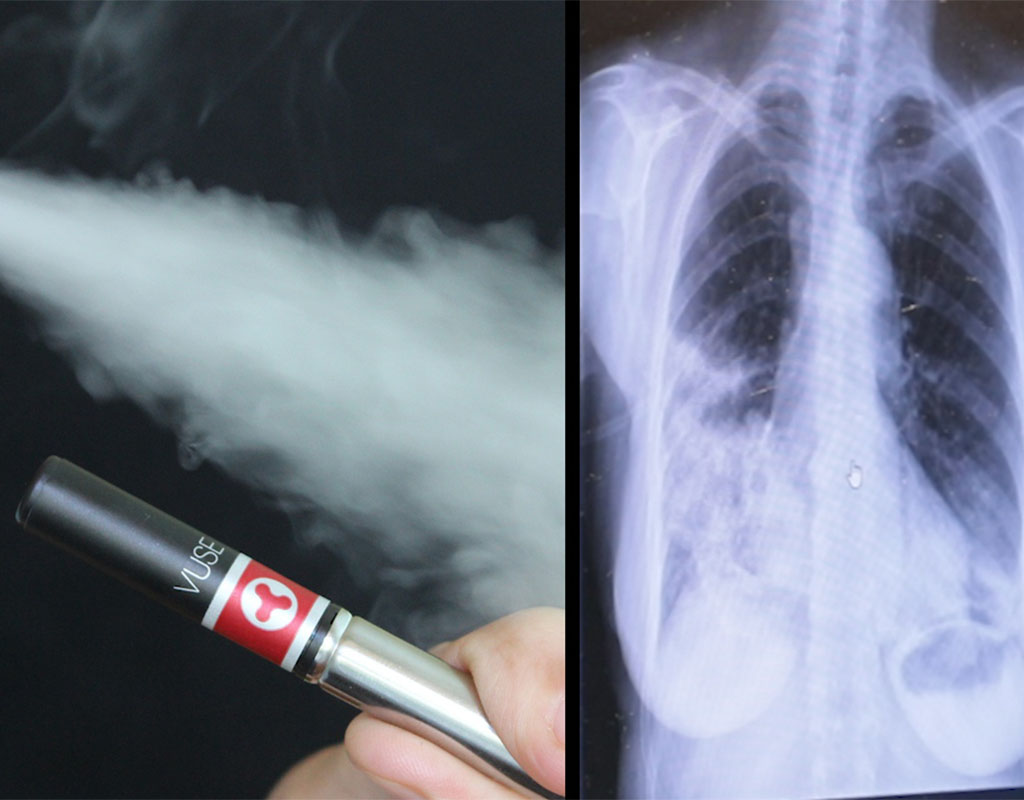

Ontario teen's vaping injury consistent with 'popcorn lung,' study Popcorn Lung Real Popcorn lung (bronchiolitis obliterans) is an uncommon type of lung disease. Popcorn lung is a condition that damages your lungs' smallest airways and makes you cough and feel short of breath. However, the inhaled vapor contains more than 7,000 potentially harmful chemicals that can damage. Bronchiolitis obliterans) is a rare condition in which lung damage starts in the small airways. Popcorn Lung Real.

Medical Professional Links 'Popcorn Lung' Disease to Vaping Popcorn Lung Real Many people believe that it is a safer alternative to smoking; Popcorn lung is a condition that damages your lungs' smallest airways and makes you cough and feel short of breath. Bronchiolitis obliterans) is a rare condition in which lung damage starts in the small airways in the lungs,. However, the inhaled vapor contains more than 7,000 potentially harmful chemicals. Popcorn Lung Real.

Rare ‘Popcorn Lung’ Linked to Chemical in Ecigarettes; Young Woman’s Popcorn Lung Real Popcorn lung (bronchiolitis obliterans) is an uncommon type of lung disease. Bronchiolitis obliterans) is a rare condition in which lung damage starts in the small airways in the lungs,. Many people believe that it is a safer alternative to smoking; Popcorn lung is a condition that damages your lungs' smallest airways and makes you cough and feel short of breath.. Popcorn Lung Real.